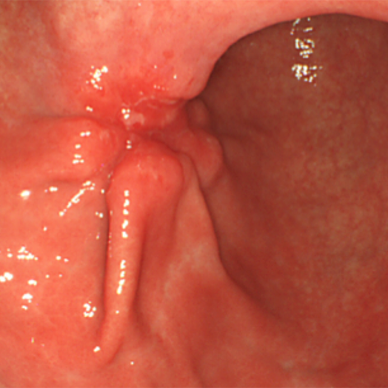

This article will review the current practice of hepatic resection for colorectal liver metastases, including the possibility of combined resection of hepatic metastases at the time of resection of the primary cancer.